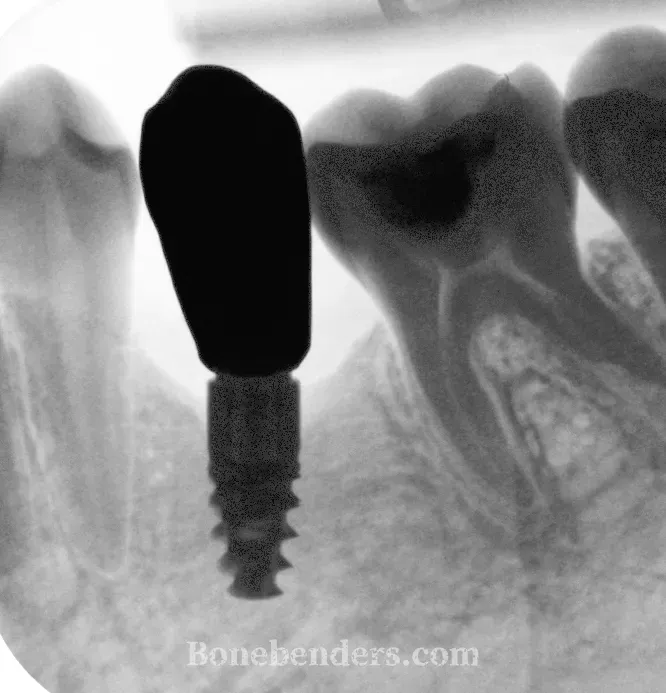

Il paziente presenta una cresta alveolare del settore posteriore sinistro mandibolare con spessore vestibolo-linguale insufficiente per il posizionamento implantare convenzionale in posizione secondo premolare. La CBCT conferma uno spessore crestale di 2 mm scarsi, inadeguato per impianti di diametro standard.

A 12 mesi: osteointegrazione completa confermata radiograficamente.